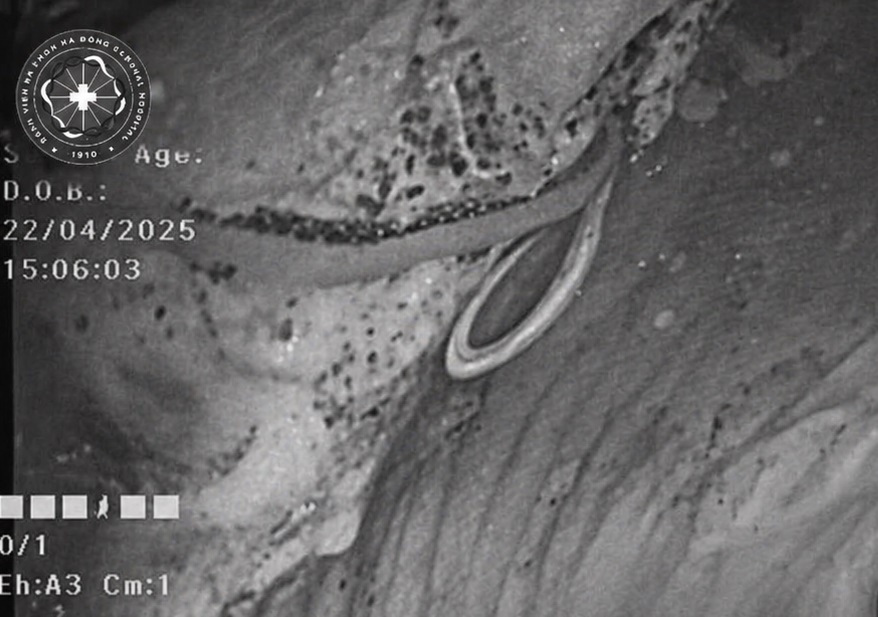

Hình ảnh kết quả nội soi đại tràng của bệnh nhân. Ảnh: BVCC.

Nội soi đại tràng cho bệnh nhân, bác sĩ chuyên khoa II Nguyễn Hợp, phụ trách Trung tâm Nội soi, ngạc nhiên khi kết quả phát hiện hình ảnh bất thường: Một ký sinh trùng dạng sợi trắng, dài, đang cuộn trong lòng ruột. Đây chính là nguyên nhân trực tiếp gây ra các triệu chứng kéo dài ở bệnh nhân.